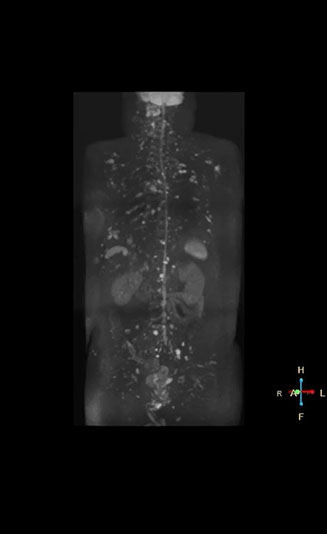

Recognizing the clinical utility of whole body MR imaging, radiologists at Kawasaki Saiwai Hospital (Kasawaki, Japan) began offering whole body diffusion weighted imaging (DWI) in 2009 for oncology patients. In 2012, the hospital installed a Philips scanner, the Ingenia 1.5T. The dStream digital architecture and highly linear gradients of Ingenia allowed them to switch to coronal – rather than axial – whole body DWI, and were key to developing a fast, high quality protocol that has led to increased referrals and decreased dependence on nuclear medicine imaging.

“Switching to coronal DWIBS – rather than axial – further shortens scan time,” says Mr. Naka. “Important is that a dS SENSE factor of 5 shortens exam time while high image quality can be maintained, thanks to Ingenia’s dStream architecture.” He adds that the coronal orientation also avoids artifacts that are specific to combining axial images.

“When we use a coronal DWIBS acquisition, we can perform a full whole body examination, including other required sequences, within 30 minutes,” he says.

“mDIXON FFE allows us to quickly get information we need to assess the presence of fat. That gives us more information when we need to diagnose bone lesions, and when we are asked to judge fat-containing lesions such as hepatocellular or renal carcinoma,” Dr. Nobusawa says. “The mDIXON fat images can help us to differentiate fatty bone marrow from bone lesions. This is especially useful in elderly people, who tend to have fattier bone marrow. The water images provide a high signal-to-noise ratio in the intestinal canal, which is valuable for visualizing lesions in the colon,” he says.

Kawasaki Sawai Hospital’s whole body protocol also includes an mDIXON FFE sequence. Because mDIXON provides images for four contrast types – water only, fat only, in-phase and out-of-phase – from a single acquisition, it is useful in many ways.

“In-phase and out-phase sagittal T1-weighted FFE images help us to visualize and further characterize bone lesions such as metastasis and bone-marrow hyperplasia that have high signal on DWI. These images are also used throughout radiotherapy, to monitor changes in the fatty bone marrow.”